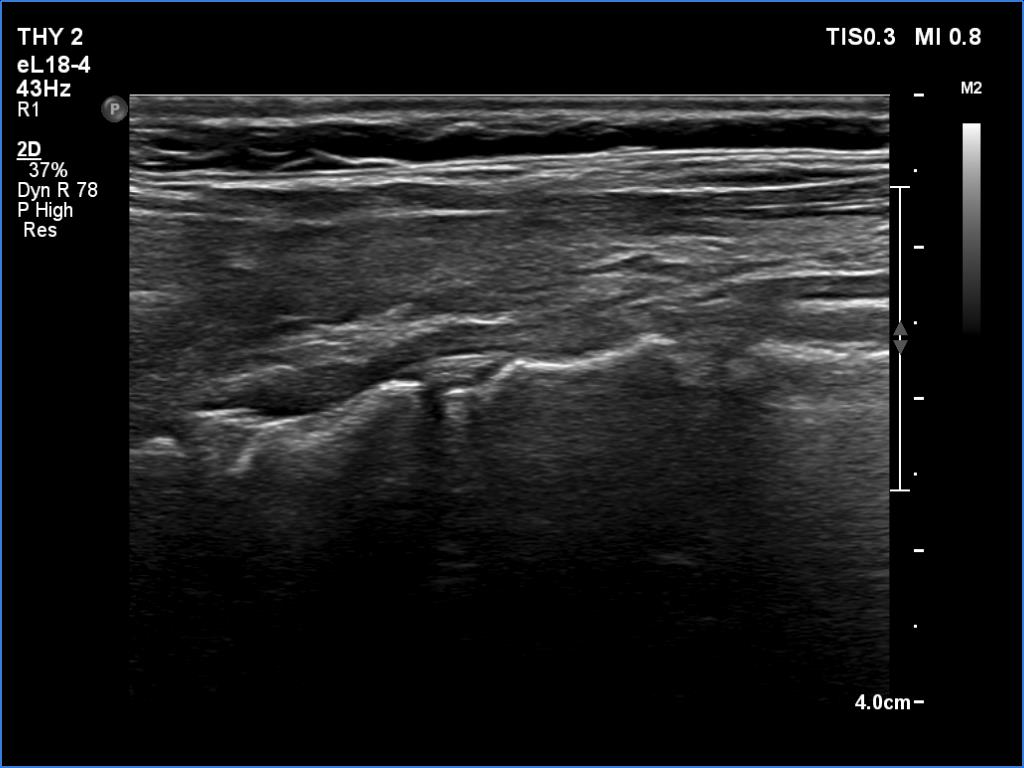

Lymphocytic thyroiditis - case 897

Follow-up investigation 6 months after the previous visit (ultrasonographic picture 5)

Left lobe, another longitudinal scan.